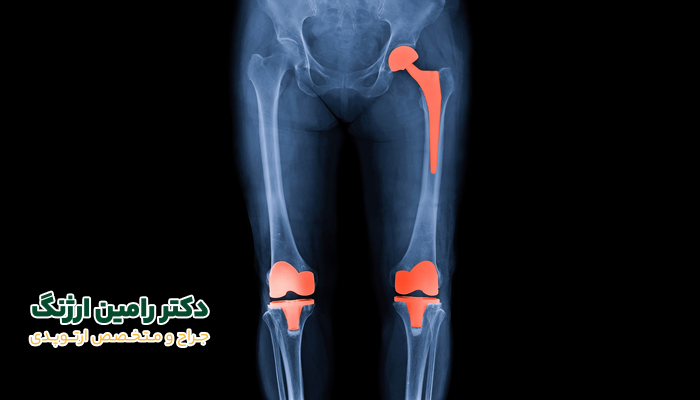

تصور کنید دوباره راحت و آزادانه قدم بزنید، بدون اینکه دردی احساس کنید یا درد شما را ناراحت کند! جراحی تعویض مفصل یا آرتروپلاستی، همان شاهکار در دنیای پزشکی است که مفاصل فرسوده را با پروتزهای پیشرفته جایگزین می‌کند و سلامت را به زانو، شانه یا لگن و سایر مفاصل شما بازمی‌گرداند.

آرتروپلاستی یا همان جراحی تعویض مفصل، یکی از رایج‌ ترین عمل‌های ارتوپدی در جهان است. در این روش، مفصل طبیعی که به دلیل آرتروز، ساییدگی، شکستگی یا بیماری‌ های دیگر به‌ درستی کار نمی‌کند و در بدن درد ایجاد می‌کند، با یک مفصل مصنوعی (پروتز) جایگزین می‌شود. این پروتز معمولاً از فلز، سرامیک یا پلاستیک‌ های خاص ساخته می‌شود و به‌گونه‌ ای طراحی شده که شباهت بسیار زیادی به مفصل طبیعی انسان داشته باشد.

• زانو: شایع‌ ترین نوع جراحی آرتروپلاستی همین آرتروپلاستی زانو است که بیشتر در افراد مبتلا به آرتروز پیشرفته یا ساییدگی غضروف انجام می‌شود. همچنین هدف آن هم کاهش درد شدید زانو و بازگرداندن مجدد توانایی راه‌ رفتن است.

• لگن (هیپ): مفصل بعدی، مفصل لگن است که در رتبه دوم بیشترین جراحی تعویض مفصل قرار دارد. بیشتر برای بیمارانی انجام می‌شود که لگن آن‌ها دارای شکستگی، آرتروز شدید و ساییدگی است. این عمل درد هنگام نشستن یا حرکت را کاهش می‌دهد.